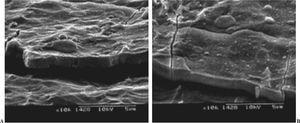

El recubrimiento no se debe disolver con el medio fisiológico en corto tiempo ni reaccionar con el metal del substrato. La reacción con el metal puede tener resultados catastróficos, ya que los productos de reacción, en general, son citotóxicos y las propiedades mecánicas del material disminuyen hasta el punto de hacer peligrar la integridad mecánica del mismo (fig. 1). La capa no debe cambiar la composición química y ésta debe ser homogénea en toda la estructura2.

Figura 1. Productos de corrosión en una prótesis recubierta con material bioactivo. Corrosión producida en un acero inoxidable 316L que fue recubierto por una capa de fosfato de calcio con presencia de silicio. Se formaron compuestos silicio-cromo que afectaron al comportamiento biológico de la prótesis, ya que son intolerables para el organismo.